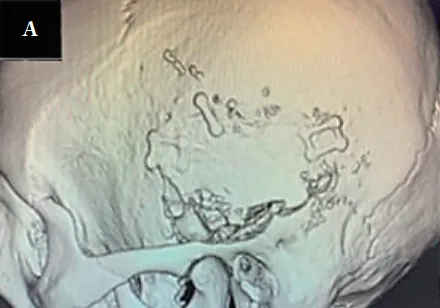

图2A:开颅手术。